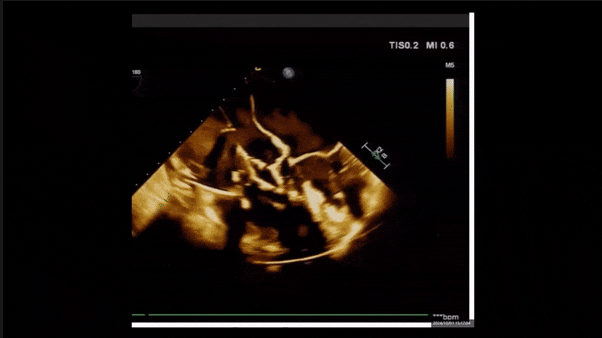

術(shù)后三維超聲

術(shù)后即刻經(jīng)食道超聲可見(jiàn),三尖瓣假體瓣膜位置合適,牛心包瓣葉運(yùn)動(dòng)狀態(tài)良好,開(kāi)閉正常,瓣周及瓣葉對(duì)合緣處未見(jiàn)明顯返流,心電圖及心包狀態(tài)較術(shù)前無(wú)明顯變化。

術(shù)后即刻返流

術(shù)后即刻返流三維

術(shù)前術(shù)后返流情況對(duì)比